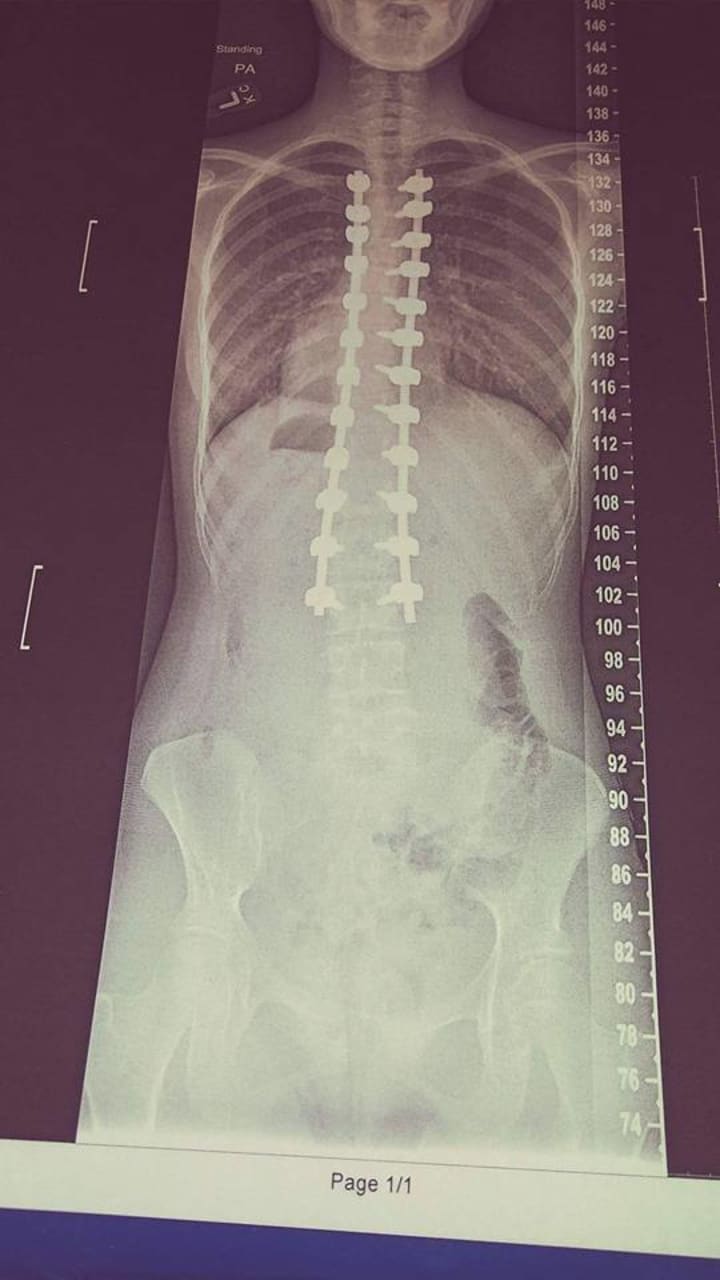

Doctors never really see what you do all day, which makes it easier for me. They don't have to tell me to sit up straight, not slouch because it will mess up my back. They don't have to tell me that I can't stay up all night because it will affect my eyes. Nothing can stop me, that's what I thought till I was in middle school and I found out that I had scoliosis. At first, I didn't care I just thought that it was gonna be fine my spine was different. Till the older I got it got worse and I just felt depressed, I felt like this is bad but I ignored it and thought that the more I ignore it and the more I stand straight it will be better. It didn't, it got worse no matter what.

The worst bullying that I've gotten was when they bullied me for my scoliosis. I can't help something like that. How they found out because I thought to brag about having a bad back would make people pity me and be nice to me, no it didn't. It made them feel like when they look at me they don't look at me like I'm a normal human. No one is normal though unless you're Barbie and have millions of money and sisters and no brothers and get whatever you want.

After my scoliosis though I didn't get bullied anymore. I mean in real life I didn't, online I still did but I know what a block button is. I wish we had really block buttons though, that would make life so much easier. Life isn't easier with extreme scoliosis surgery, you can't do what you want to do anymore, but I still have one thing that the surgery didn't take away from me, which was my life and my personality.